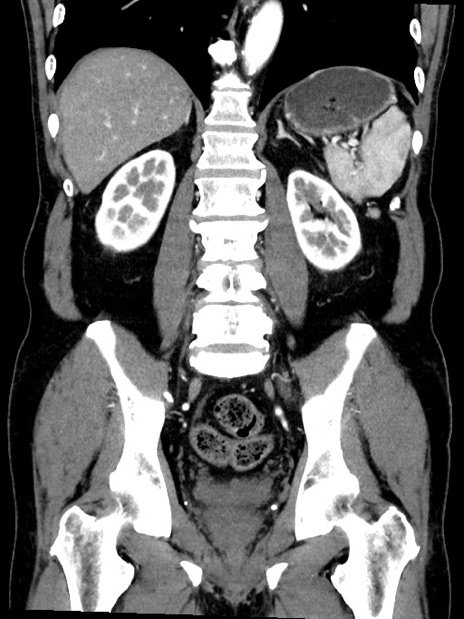

症例35(冠状断像)

【症例】70歳代 男性

【主訴】腹部膨満、嘔吐

【現病歴】昨日より腹部膨満感出現。本日増悪し、仙痛出現。嘔吐あり、受診。

【既往歴】糖尿病、胆摘後

【身体所見】BP 149/80mmHg、HR 74/min、BT 35.9℃、腹部:膨満、軟、圧痛なし。腸雑音減弱あり。上腹部正中切開瘢痕あり。

【データ】WBC 13500、CRP 1.72